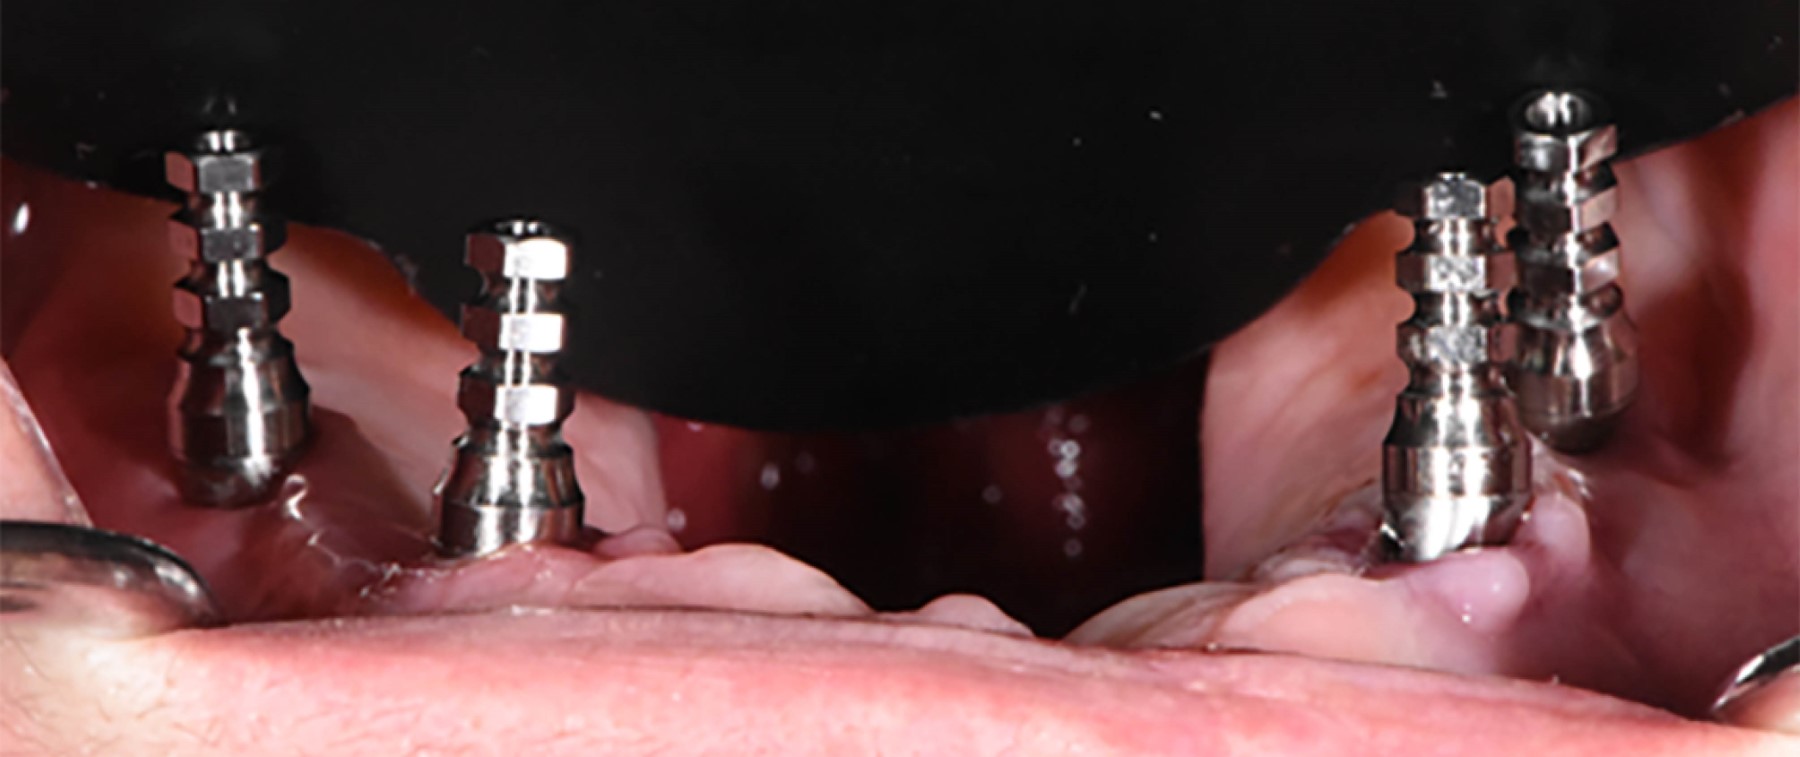

Under general anesthesia and nasotracheal intubation, four Zygoma GMTM Neodent implants with a diameter of 4.0 mm with Grand Morse connection were placed, the Slot technique was used according to the milling protocol of the commercial house, at the level of 16, 13 and 26, implants of 40 mm long and at the level of 23 a 45 mm long implant; all with adequate primary stability (insertion torque greater than 45 Nw/Cm during placement of all implants) (Figure 4). Finally, the respective covers were installed. Bichat ball implants were covered bilaterally and closure was performed by first intention with 3/0 Vicryl suture.

Four months after the first intervention, the second phase surgery was performed at the IPS CES in Sabaneta-Antioquia, with a local anesthetic technique. On this occasion, angled conical mini-pillars were installed as follows: 45° × 1.5 mm in the area of 16, 45° × 2.5 mm in area of 13, 45° × 1.5 mm in area of 23 and 45° × 1.5 mm in area of 26. Parallelism was verified and they were covered with respective protection cylinders from the Neodent commercial house.

Figure 4